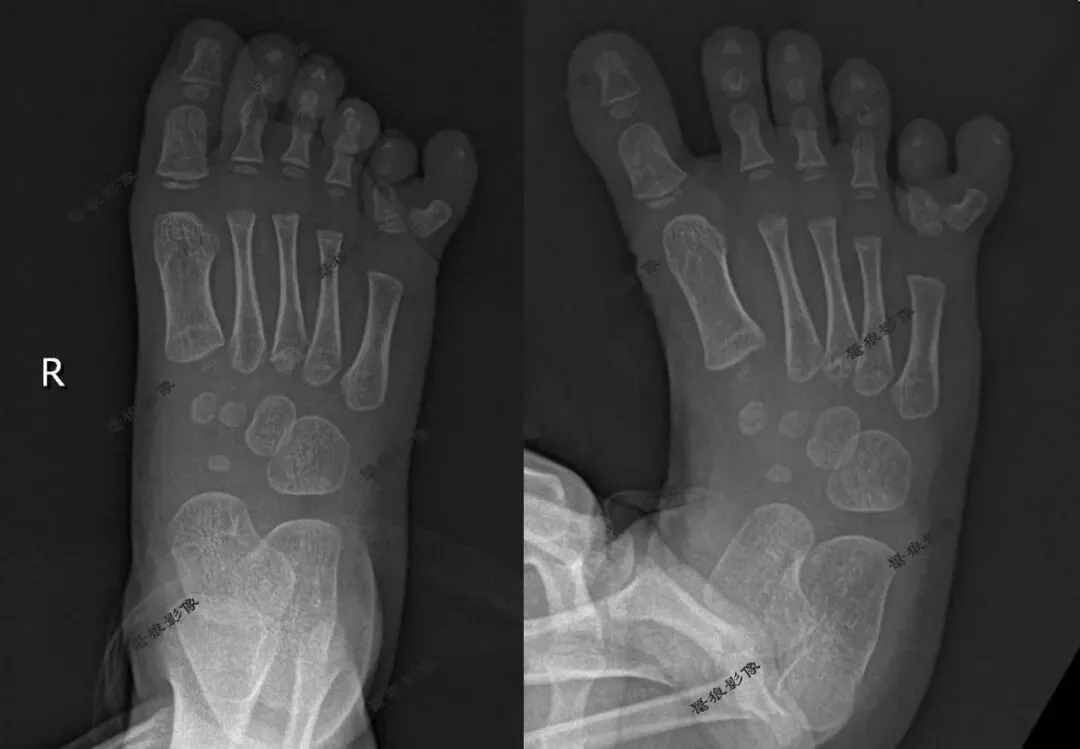

案例一:

二、右足第5趾多趾畸形。